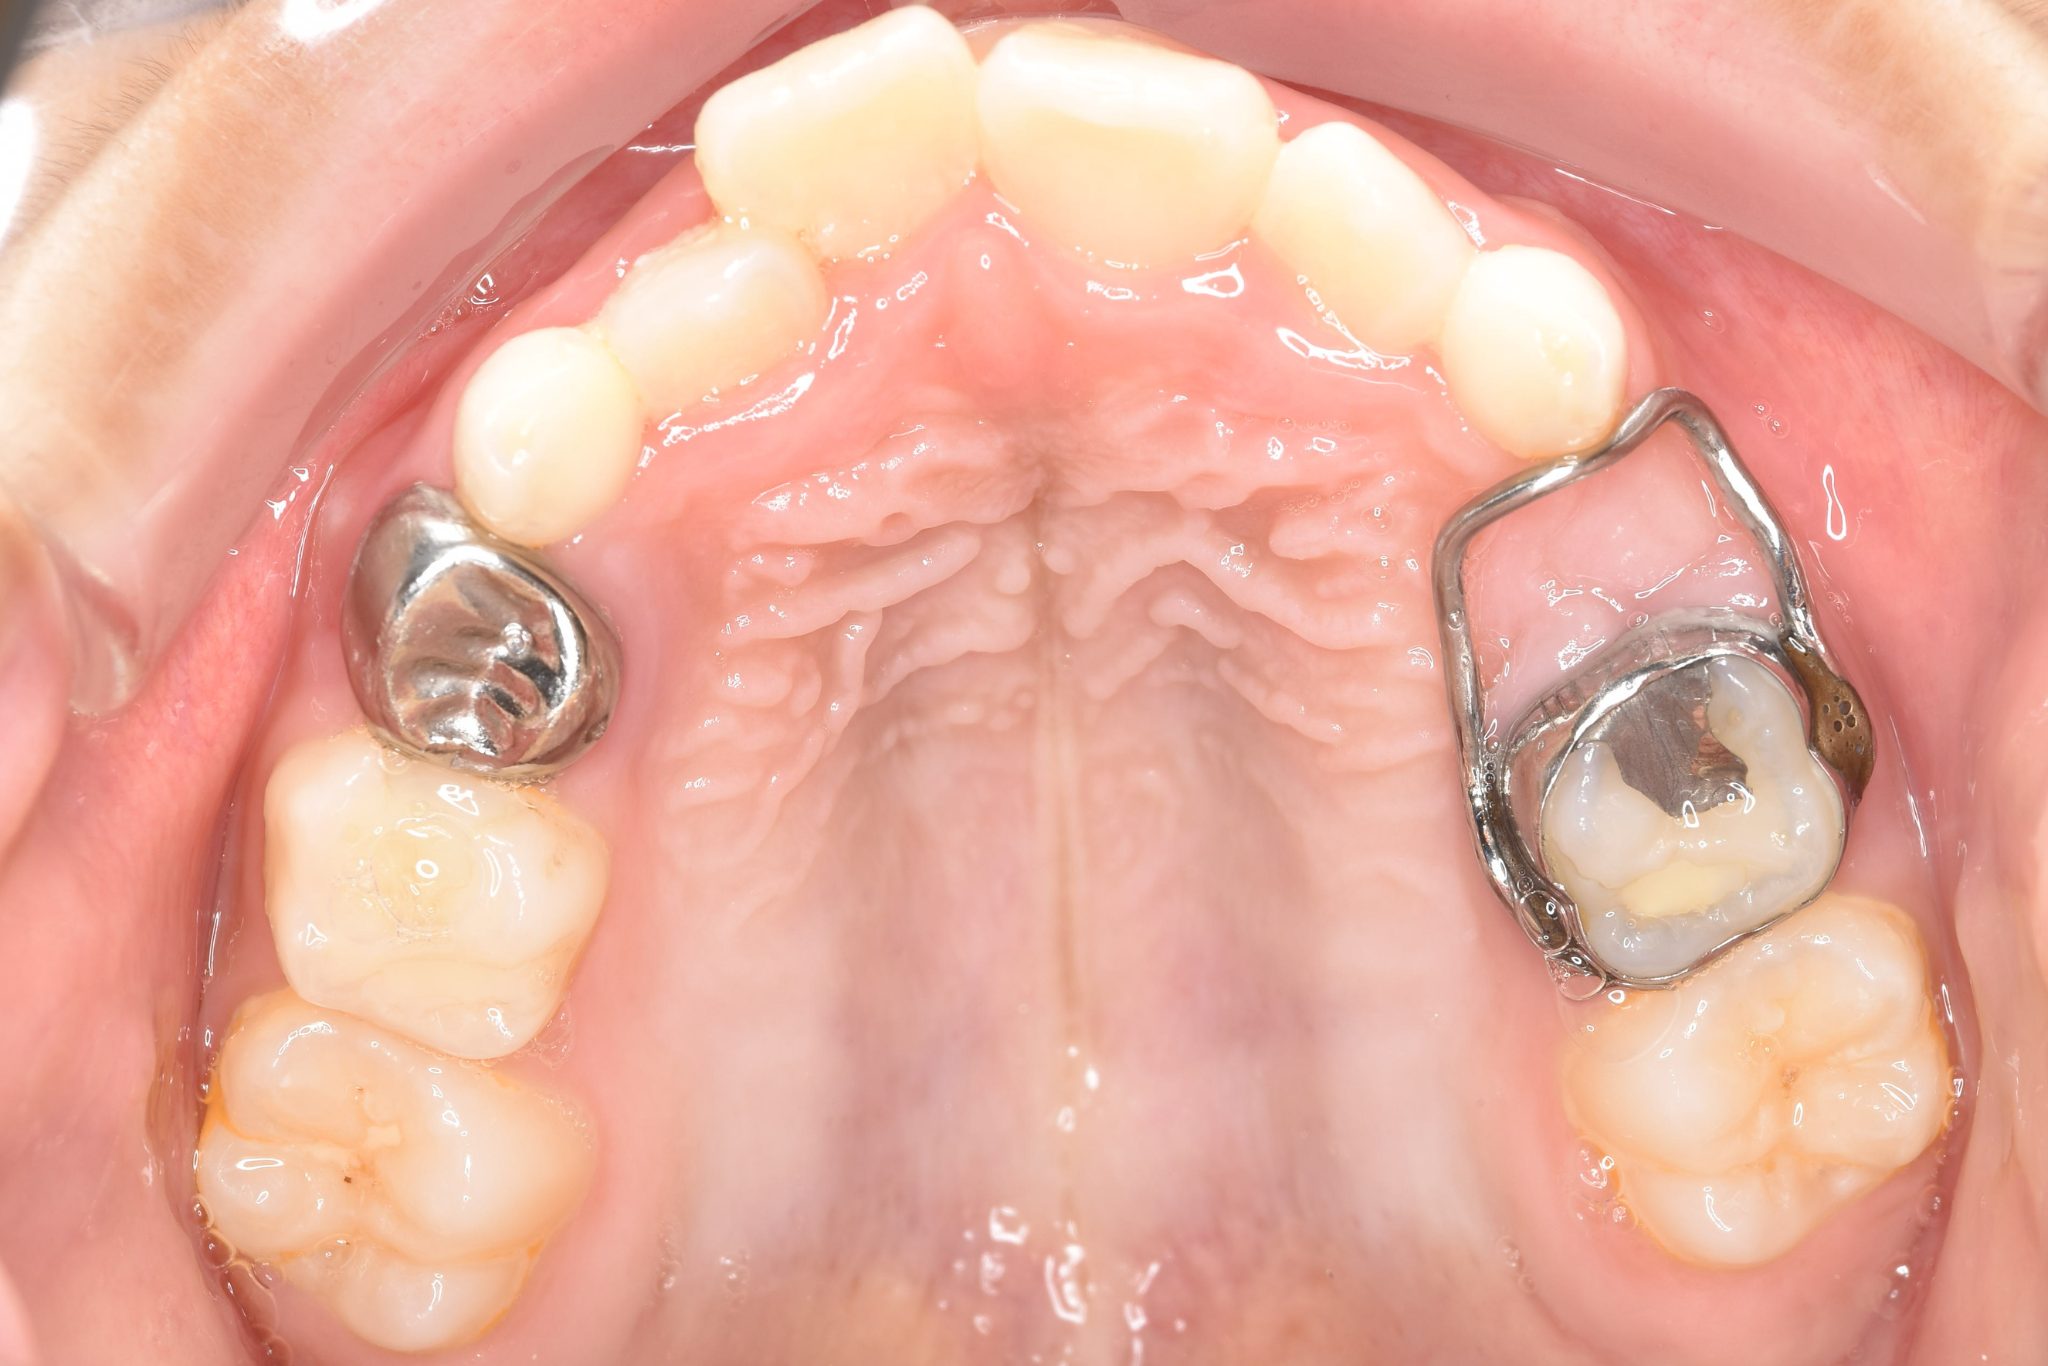

アフター

子どもの矯正治療|症例_169

施術内容 上顎急速拡大装置と下顎リンガルアーチを用いて上下顎骨を拡大した。

その後マウスピース型矯正装置で歯牙を配列し良好な咬合を獲得した。

治癒期間 3年5ヶ月間